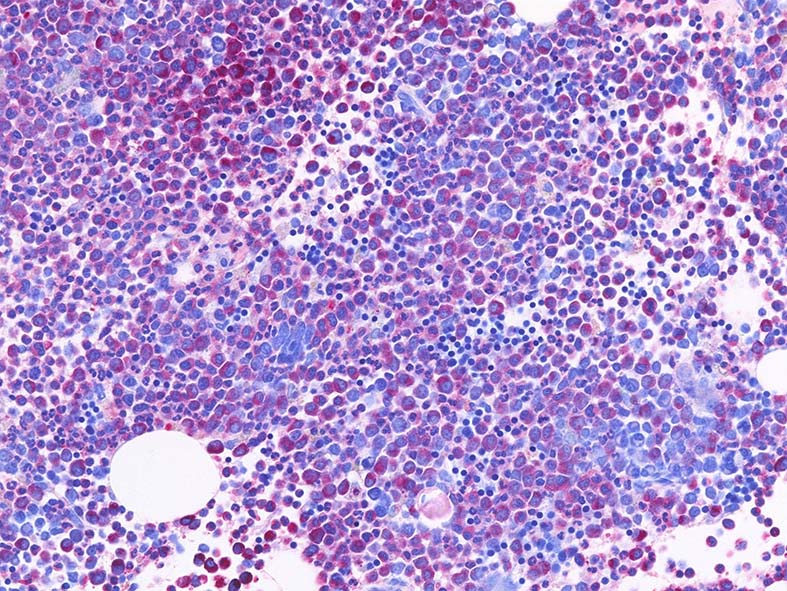

Naphtohl-ASD-CAE Fig.01

Fig.01: hypercellular marrow. ASDで赤染する細胞の増加=granulopoietic hyperplasiaがある.

Fig.02: 幼若な顆粒球が増加している. 赤芽球は散在しており血島は不明瞭である. 過形成髄なのにFig.02に成熟大型巨核球はみられない.

Fig.03: granulopoietic hyperplasia. 成熟顆粒球の増加もある.